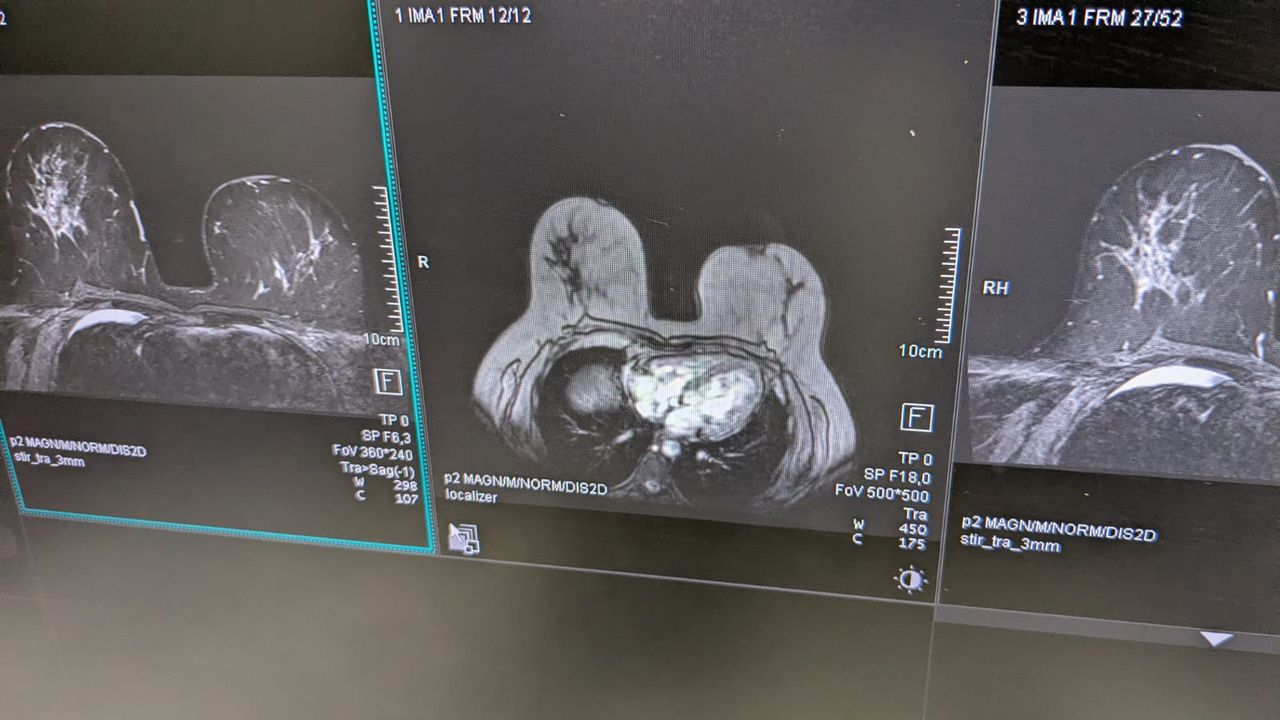

Svolgo tutte le principali indagini senologiche, tra cui mammografia, ecografia mammaria, visita senologica e risonanza magnetica della mammella, seguendo la donna anche nelle fasi successive dell’iter diagnostico, quando necessario, con continuità e competenza.

**Si eseguono RM mammella con m.d.c. con apparecchiatura di nuovissima generazione GE 3 Tesla (tra le poche in uso in Italia) e TC per lo studio dei vasi coronarici con una TC Siemens di nuovissima generazione**